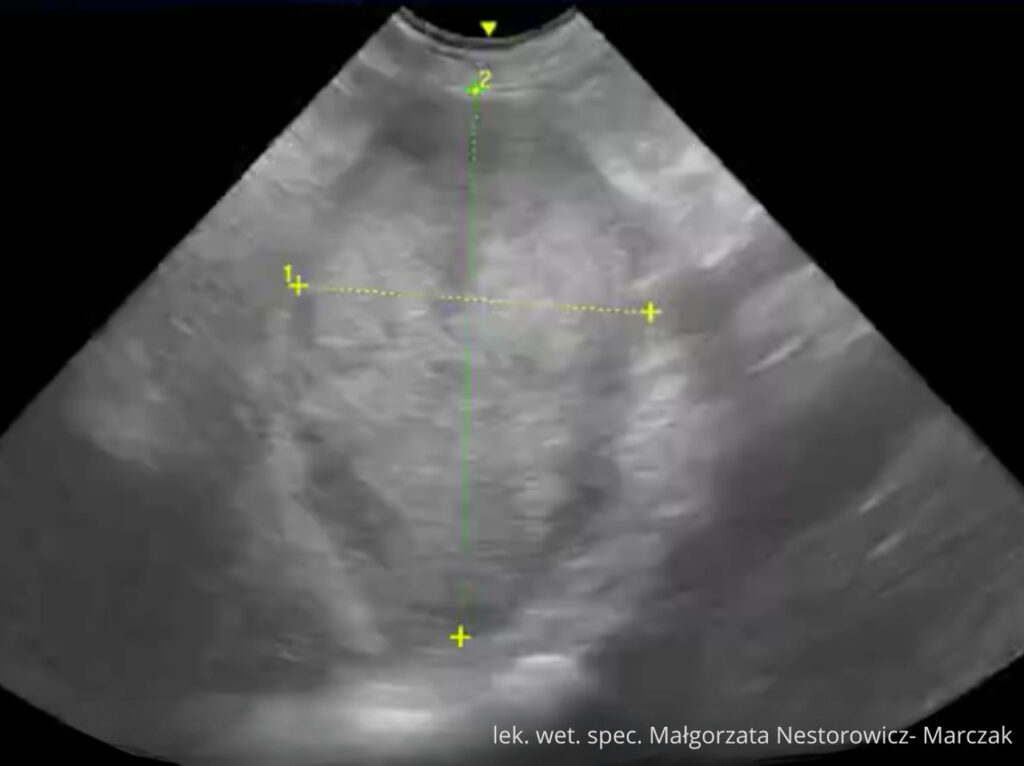

Udostępniamy cały moduł „Wątroba i drogi żółciowe” jako próbkę kursu.

To pełnowartościowy moduł szkoleniowy (niemal 2 godziny materiału), który pozwoli Ci zobaczyć, jak w praktyce wygląda nauka w kursie. Dzięki niemu sprawdzisz:

lek. wet. spec. Małgorzata Nestorowicz- Marczak

Na co dzień pracuje z małymi zwierzętami (psy, koty) w Warszawie wykonując badania USG tkanek miękkich m.in. jamy brzusznej, szyi, klatki piersiowej. Uczestniczy jako prelegent oraz trener części praktycznej w kursach USG organizowanych dla lekarzy weterynarii.